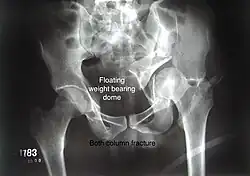

Combined both column fractures These are the most complex injuries. Here the weight bearing roof or dome of the acetabulum is a floating piece. This adds to complexity of management.

Diagnosis

All three x-ray views plus CT scan is a must for diagnosis and management of this complex injury.

Treatment

Like any other acetabular fracture, if the femoral head is dislocated out of the socket, early reduction into socket is a priority. However, in this injury, non-operative treatment rarely gives satisfactory results. Surgical management is ideal. The choice of approach rests with the surgeon, but going from front, or anterior approach is must. The posterior injury may be tacked with anterior approach by experienced surgeon. If the patient is unfit to undergo major surgery due to any reason, longitudinal traction to achieve secondary congruence of hip may help to restore hip function, though partially.